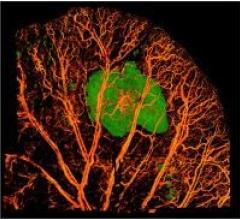

December 30, 2013 — A University of Alabama at Birmingham surgical team has performed the first surgery using a virtual ...